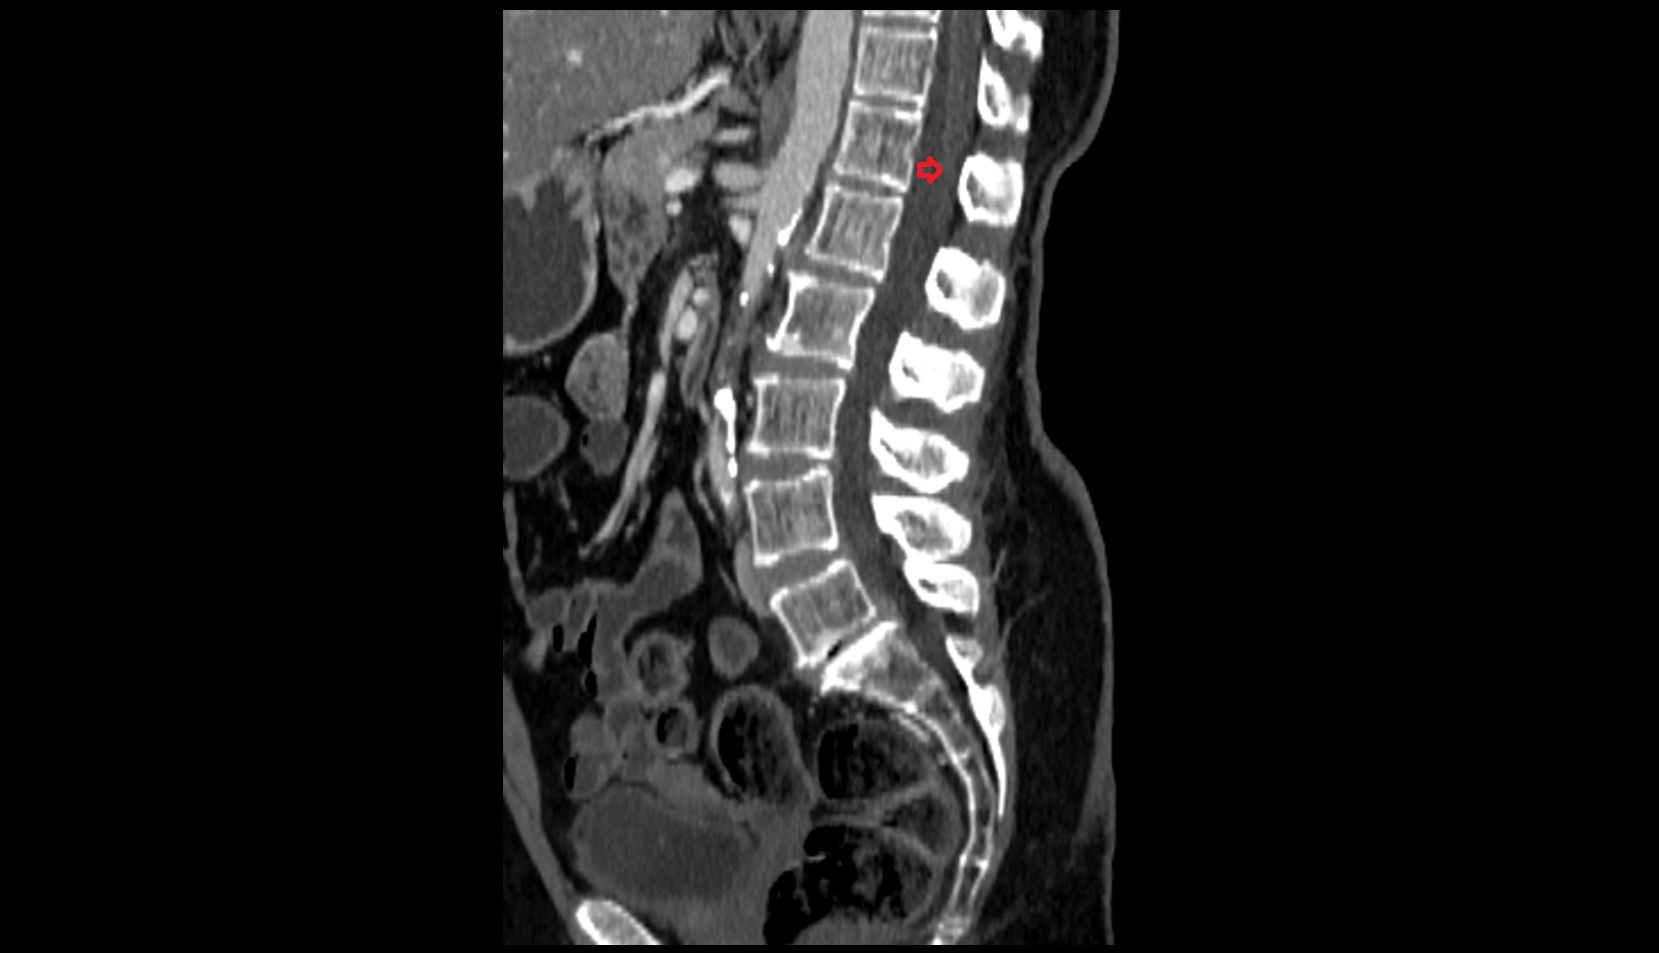

- Spinal dura mater

- Spinal epidural space

- Annulus fibrosus of intervertebral disc

- L4–L5 Intervertebral Disc

- L3–L4 Intervertebral Disc

- L2–L3 Intervertebral Disc

- L1–L2 Intervertebral Disc

- T12–L1 Intervertebral Disc